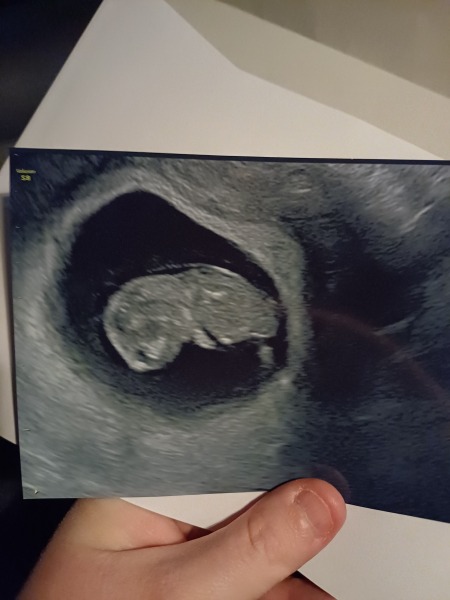

Hi everyone so sorry for the radio silence so glad everyone’s scans have been going well and best wishes to everyone who’s still waiting! It’s deffo been a nervous wait the last few weeks. We went in and they’ve confirmed that we have one healthy baby, with a heartbeat, moving around measuring at 8w 5 days which is exactly what it always should have been.

The other twin sac unfortunately never developed its still completely empty and has shrunk so just hoping my body absorbs it which it seems to be doing. I’m feeling quite relieved about it to be honest as was quite daunted with the idea!!